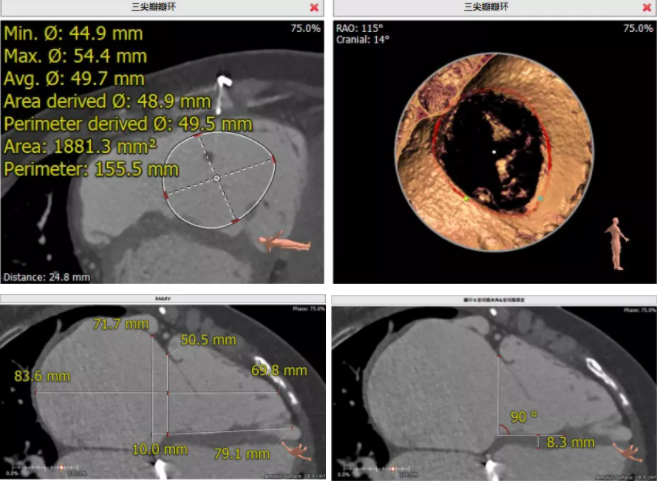

術(shù)前CT評估